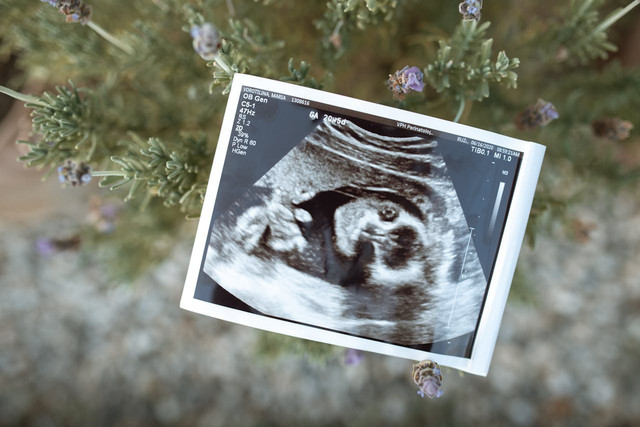

Perkembangan embrio adalah proses biologis yang kompleks dan menakjubkan di mana sebuah organisme hidup berkembang mulai dari sel tunggal hasil pembuahan hingga menjadi janin yang siap lahir. Proses ini melibatkan pembelahan sel yang cepat, diferensiasi jaringan, dan pembentukan organ-organ penting yang menentukan bentuk dan fungsi tubuh. Simak uraian ini hingga tuntas untuk mengetahui secara rinci tentang proses perkembangan embrio.

Proses perkembangan embrio dimulai dengan fertilisasi, yaitu penyatuan sel telur dan sperma. Berdasarkan jurnal bertajuk Human Biology yang dipublikasikan Open Textbooks Minnesota, fertilisasi adalah proses di mana gamet menyatu untuk membentuk zigot, dan sel telur serta sperma masing-masing mengandung satu set kromosom.

Setelah proses pembuahan terjadi, perkembangan embrio dimulai dengan pembelahan sel yang disebut cleavage. Menurut jurnal bertajuk Concepts of Biology dari Open Textbooks Canada, setelah sel pertama hasil pembuahan terbentuk (disebut zigot), sel ini mulai membelah berulang kali hingga membentuk struktur awal yang disebut blastula.

Menurut StatPearls NCBI, pada tahap blastokista (sekitar lima hari setelah pembuahan) embrio sudah terdiri dari sekitar 50 sampai 150 sel. Pada tahap ini, sel-sel mulai memompa cairan ke bagian tengah sehingga terbentuk sebuah rongga. Rongga ini membuat blastokista mengembang.

Tahap berikutnya dalam perkembangan awal adalah organogenesis, yaitu proses pembentukan organ tubuh. Tahap ini dimulai pada minggu ketiga sampai minggu kedelapan kehamilan dan terus berlangsung hingga bayi lahir.

Menurut Path Fertility, setelah usia kehamilan 10–12 minggu, embrio memasuki tahap perkembangan berikutnya dan mulai disebut sebagai janin. Pada tahap ini, embrio sangat rentan.